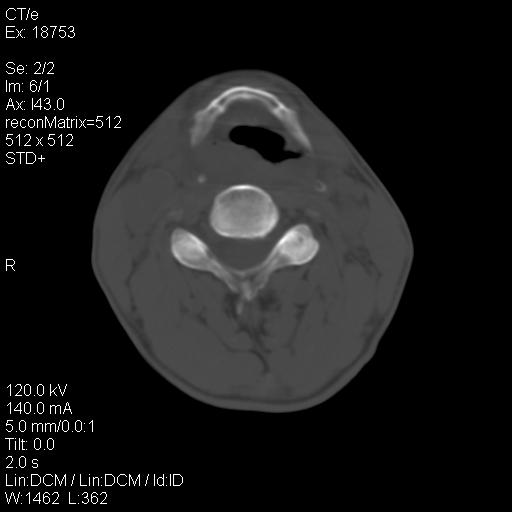

标题: CT21693:男 58岁 右侧咽部疼她2天余 PE:右侧扁桃体肿大 压痛 [打印本页]

标题: CT21693:男 58岁 右侧咽部疼她2天余 PE:右侧扁桃体肿大 压痛

右化脓性扁桃体炎症伴咽后壁脓肿形成.